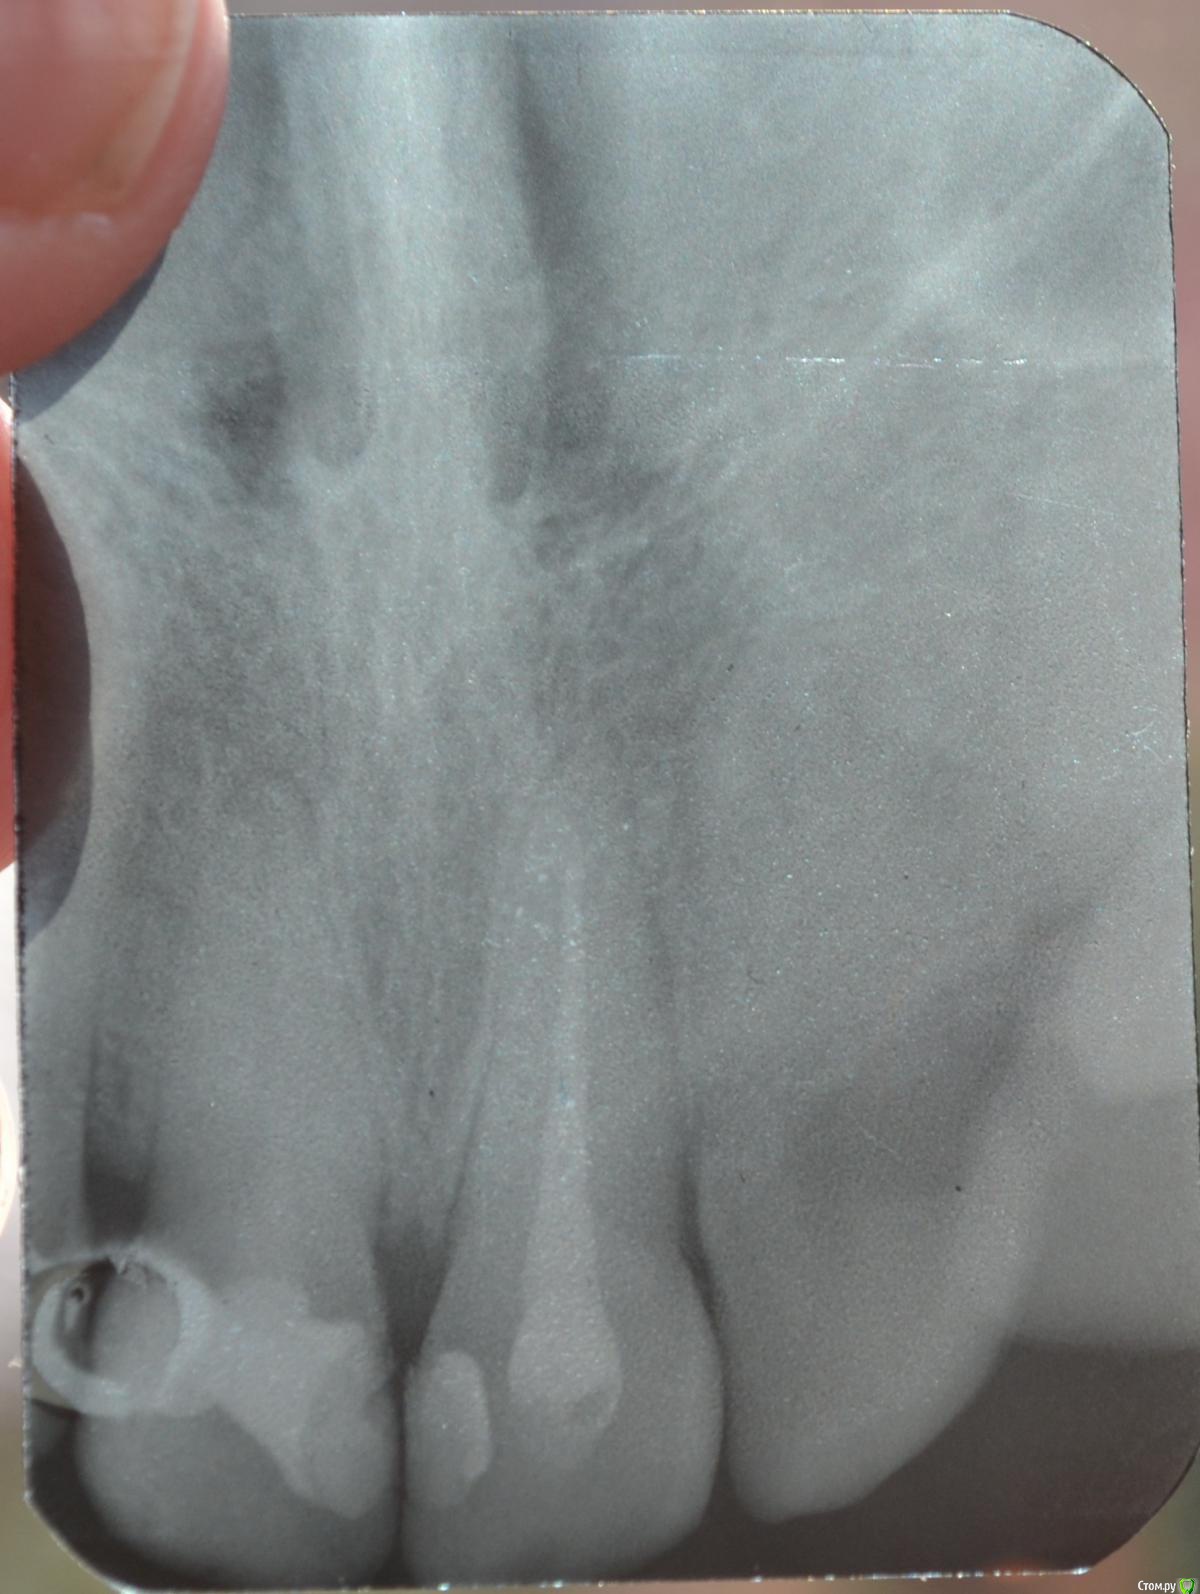

Llllll Опубликовано 11 июля, 2015 Автор Поделиться Опубликовано 11 июля, 2015 1 справа верхний, до того как открыли недавно каналы. Ссылка на комментарий

Llllll Опубликовано 12 июля, 2015 Автор Поделиться Опубликовано 12 июля, 2015 Лучше бы прицельный снимок проблемного зуба(на ОПТГ ничего не видно).Это 2 снимка этого зуба, несколько раз сфотографировала, чтоб лучше было видно. Ссылка на комментарий

Llllll Опубликовано 12 июля, 2015 Автор Поделиться Опубликовано 12 июля, 2015 И есть ли воспаление корня на снимке? (правого или левого). Вообще врач думал во вторник удалять передний зуб, который болит. К другому врачу не могу пойти, так как город маленький, и врачей всего несколько. Это уже третий врач у которого была, и никто не знает что с зубом делать, и вообще от него ли это( Ссылка на комментарий

Llllll Опубликовано 16 июля, 2015 Автор Поделиться Опубликовано 16 июля, 2015 Сегодня делали рентген еще раз, и увидели на 1 зубе справа (тот, который болит) на самой верхушке корня кусочек инструмента. Рентгена нету, так как его на компьютере только смотрели. Сказали что достать его нельзя. Что делать? Ссылка на комментарий

Llllll Опубликовано 27 июля, 2015 Автор Поделиться Опубликовано 27 июля, 2015 Вот еще делали рентген с иголкой в зубе. Ссылка на комментарий